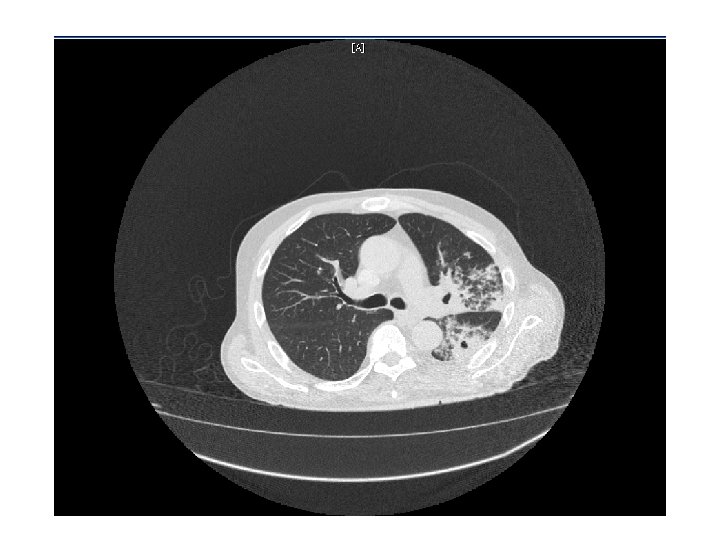

CT Chest • Multiple cavitary lesions • Largest left lung apex 3. 8 x 4. 7 cm with nodular thickened wall • Smaller cavitary lesions in L lung base • R lung: smaller areas of ground-glass opacities with areas of tree in bud appearance.